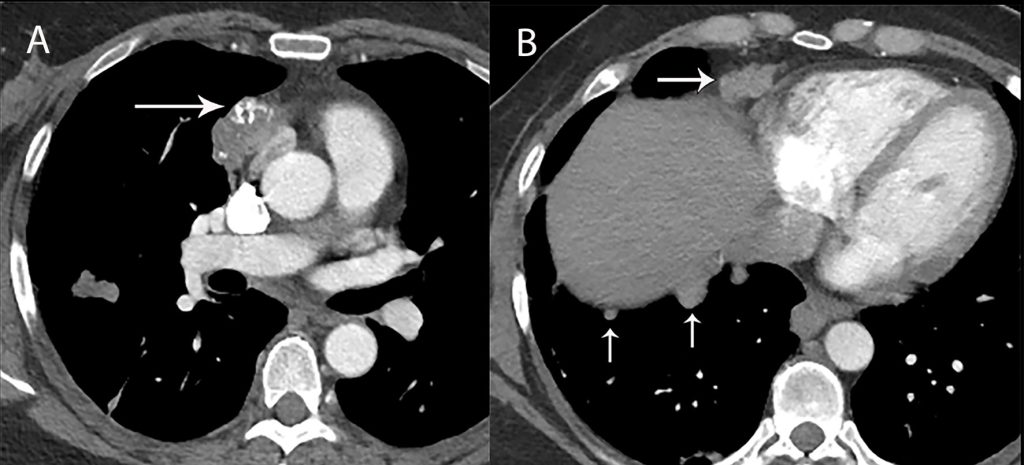

- CT scan or MRI for detailed imaging of the tumor and surrounding tissues

- Biopsy to obtain a tissue sample for microscopic examination